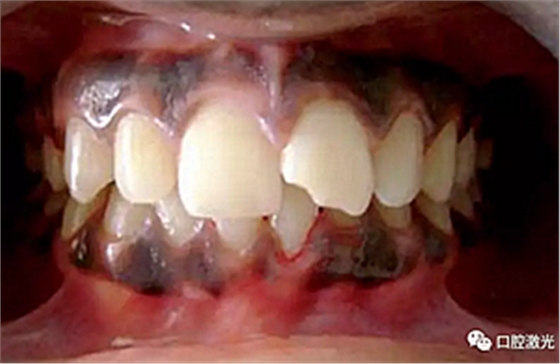

患者22岁,女性,主诉牙龈发黑。口腔检查显示牙龈部位呈黑色,但软组织健康,没有表皮粗糙或水肿现象。计划使用半导体激光进行治疗。手术前患者无需表麻或局麻。采用光纤接触方式,激光功率设定为1.5W至2W,连续模式。气化黑色牙龈区域上皮组织。不断重复该过程,直至足够深度的牙龈软组织表皮被去除干净。患者术后需采用漱口水进行口腔护理。

术中